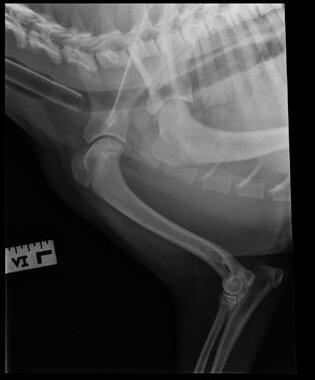

An 8-month-old female desexed Labrador retriever cross presented for a 4–6-week duration of left forelimb lameness.

On clinical exam, there was mild pain on manipulation of both shoulder joints.

Q. What is your radiological diagnosis?